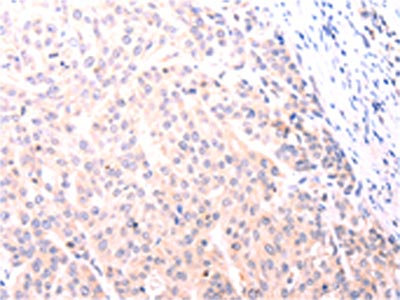

The image on the left is immunohistochemistry of paraffin-embedded Human lymphoma tissue using CSB-PA439037(NFKBIE Antibody) at dilution 1/25, on the right is treated with fusion protein. (Original magnification: ×200)

The image on the left is immunohistochemistry of paraffin-embedded Human esophagus cancer tissue using CSB-PA439037(NFKBIE Antibody) at dilution 1/25, on the right is treated with fusion protein. (Original magnification: ×200)